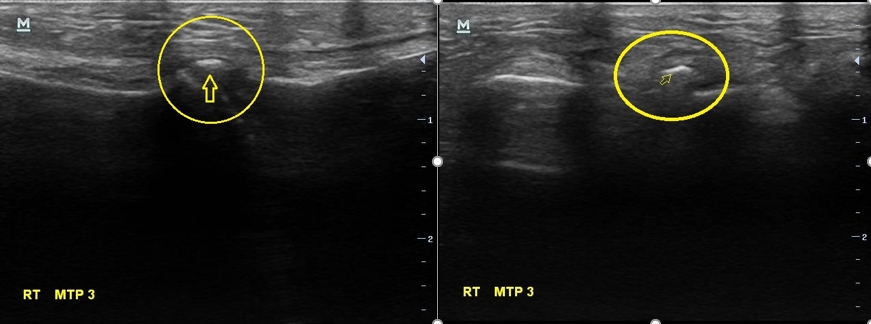

나 : 초음파에서 여기 하얗게 보이는거 있죠?

여성 : 네 보이네요...

나 : 이건 둘 중 하나인데요.... 첫번째는 금이 갔던 흔적인데.... 다친적은 없다고 하셨으니... 제 생각엔 석회 조각인거 같네요

여성 : 석회요?

나 : 네 석회성 건염이라고 해서 관절이나 힘줄 부위에 석회 조각이 생기고 이게 갑자기 염증을 만드는 경우가 가끔 있습니다.

이 여성의 병명은 '석회성 건염'이었습니다. 석회성 건염이라는 것은 우리 몸 관절부위에 석회가 쌓이면서 덩어리를 만들고 이게 염증을 만들어서 통증이 발생하는 병을 말합니다.